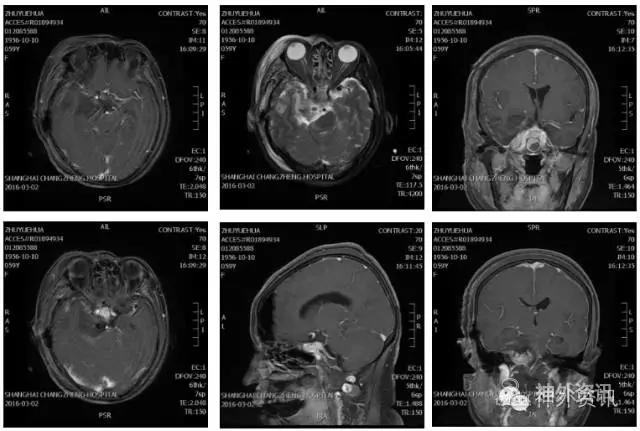

根据影像学资料显示病变所累及的范围,我们选择了颧弓-翼点加Kawase入路,用颧弓-翼点入路充分暴露前床突、中颅底,切除前床突附近和中颅窝底肿瘤;镜下打开Kawase三角,剪开硬膜切除后颅窝肿瘤,充分减压后再分离肿瘤边界,基本全切肿瘤,颅神经保护良好。最后磨除基底增生的骨质;逐层关颅。术后即刻复查增强MRI,显示肿瘤切除满意。患者拆线后出院。

术后影像学资料